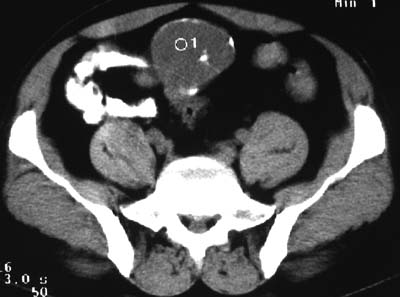

一、女,43岁,下腹部不适,子宫增大并可触及一硬物,活动度大。

典型的盆腔畸胎瘤。

病例1、盆腔畸胎瘤。病例2、盆腔占位压迫膀胱?还是膀胱占位?强化吧!

典型的盆腔畸胎瘤伴子宫肌瘤。

例1:畸胎瘤;

病理1.盆腔畸胎瘤和并子宫肌瘤

病例1、盆腔畸胎瘤,子宫体积增大,子宫肌瘤?病例2,囊腺瘤?

病例1,盆腔畸胎瘤并子宫肌瘤;病例2,囊性肿块,周围有壳状钙化,膀胱受压改变,考虑:脐尿管囊肿并感染,畸胎瘤?

考虑盆腔内畸胎瘤,子宫体积增大,建议增强扫描除外子宫病变